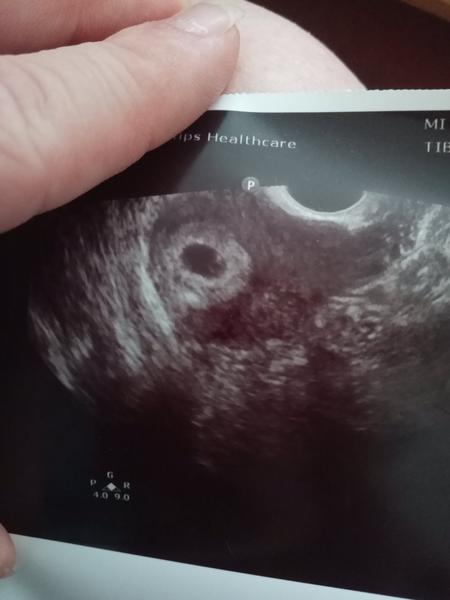

@zuzsat môžem sa spýtať ako ti robili sono? Či cez brucho alebo vaginálne? Ja som 19.5. bola na sono so špinením, spravili mi sono cez brucho a mala som iba gestačný vak a zodpovedal veľkosti 6+0, cez vaginálne sono už bol vidieť drobec + akcia srdiečka, ale strašne to bolo miniatúrne... Ja som to ledva videla...

@zuzsat ja som mala podľa sona 6+0 takto, ledva to bolo vidieť a aj to robili vaginálne, lebo cez brucho som to mala prázdne ako ty na foto.. Možno si mala len posunutú ovuláciu 🤞❤️ silno silno silno držím všetky prsty, ktoré na tele mám 🙏🤞❤️

@levandulova111 robili vaginalne sono. Na tom tvojom je aspon zltkovy vak ci babo. Ja som prazdna no... Uvidime. Drzim ti silno palce

Som 6+2, podla sona 5+3tt.... Hcg 5671... A gestacny vak 9mm a prazdny.bez zltkoveho vaku... Keby aspon ten bol tak je sanca se sa plod objavi ale takto tomu neverim